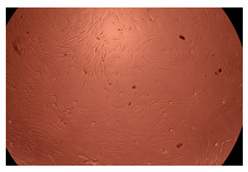

2.4. In Vitro Cytotoxicity Analysis

| Control |  |  | |

| Cop B | 10 µg/mL |  |  |

| 50 µg/mL |  |  | |

| 100 µg/mL |  |  | |

| Cop B/IMC = 10/1 (wt/wt) | 10 µg/mL |  |  |

| 50 µg/mL |  |  | |

| 100 µg/mL |  |  | |

| Cop B/Dorzolamide = 10/1 (wt/wt) | 10 µg/mL |  |  |

| 50 µg/mL |  |  | |

| 100 µg/mL |  |  | |